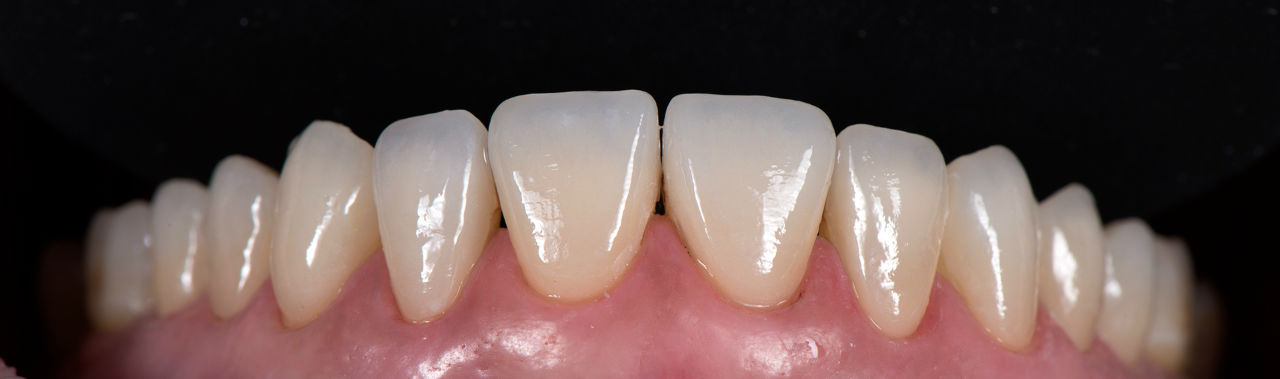

Случай 1: Дигитален дизайн на усмивката в Дента Консулт

Лечение без импланти